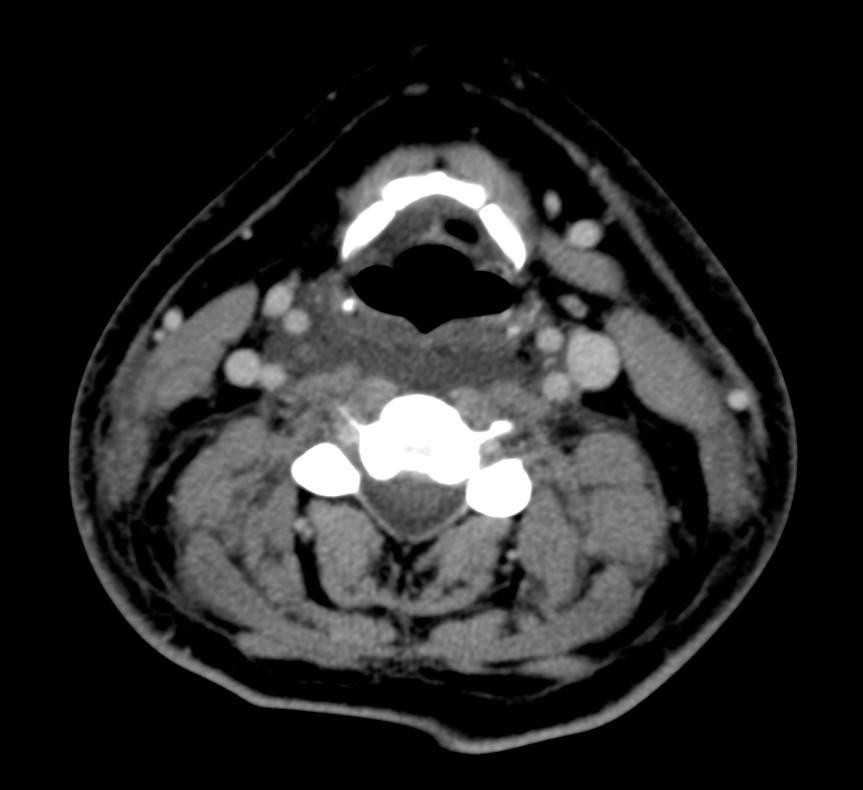

Síndrome de Lemierre: Tras una infección de la orofaringe, se produce tromboflebitis de vasos de cuello. Suelen ser infecciones asociadas con comobilidades tales como cirugía o radioterapia.

- Los defectos de repleción en la TC con contraste indican trombosis.

- La afectación de la grasa perivascular indica proceso inflamatorio.

- Si hay afectación de la vena yugular interna, existe alto riesgo de migración de émbolos sépticos a los pulmones. Por tanto, dada la gravedad, es fundamental realizar además una TC de tórax y es el radiólogo el que debe sugerir o establecer el diagnóstico de la enfermedad en un primer momento.

- La afectación de la arteria carótida puede ocasionar importantes consecuencias. Suelen ser infecciones asociadas con comobilidades tales como cirugía radioterapia de neoplasias en el cuello. Se puede producir la afectación de la vasa vasorum ocasionando necrosis mural, celulitis, abscesos o formación de seudoaneurismas y/o disecciones.

En el estudio del tórax (no se muestra) no se evidenciaron alteraciones.